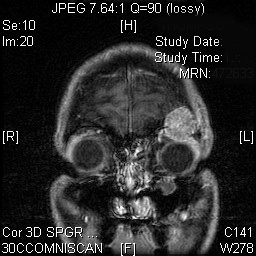

Fortunately, orbital tumors are very rare. There are over 1500 different tumors that can affect the orbit. The majority of these tumors are benign. These tumors cause problems because of their location and proximity to vital structures and organs including the eye, the muscles that move the eye, the lacrimal gland, the nerves and vessels of the orbit, the sinuses and the brain. Occasionally, a malignant tumor may involve the orbit primarily or through spread from an adjacent or distant tumor. These lesions not only cause problems because of their proximity to vital structures, but also the risk of spread to adjacent and distant organs.

Most tumors of the orbit cause symptoms including protrusion of the eye, pain, double vision and redness. Many of these tumors require a biopsy to determine the nature of the lesion and appropriate treatment. Surgery in this small space with many vital structures is very difficult and tedious.